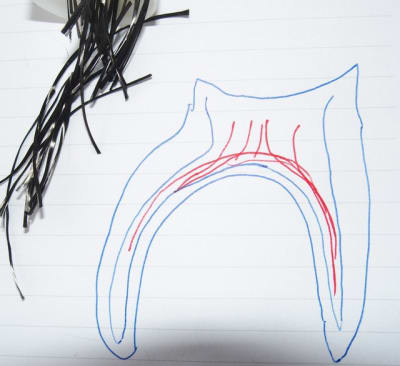

Les indications d'un ancrage radiculaire (ic ou RCR avec tenon) sont dictées par le contexte clinique.

Après pour choisir entre l'IC et la RCR avec tenon :

la RCR avec tenon doit être privilégiée à chaque fois que les conditions cliniques le permettent (pour des raisons de préservation tissulaires). Ce choix ne peut être établi avec certitude qu'après avoir effectué la préparation coronaire périphérique...

Comme cela a déjà été dit, pour la RCR avec tenon, il faut :

- au minimum 3 parois résiduelles présentant une épaisseur minimal d'1 min et une hauteur d'au moins la moitié de la hauteur prothétique ;

- la limite la plus cervical doit être supragingivale ou tout du moins permettre cliniquement la réalisation d'un joint étanche ;

- les dents trop petites, ou trop plates contre indiquent la réalisation de RCR foulées avec ou sans tenon ;

Juste un dernier point dicté par le bon sens : lorsqu'un traitement endo semble "moyen", mieux vaut éviter de mettre des choses difficile à déposer dans le canal...